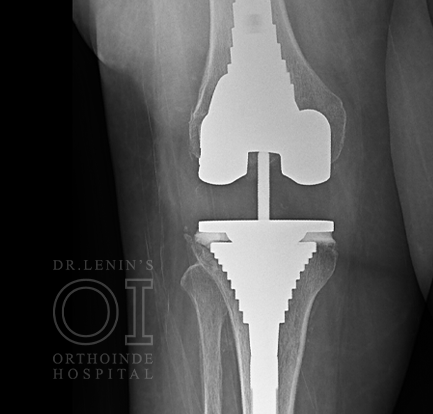

If the procedure is a simple replacement of the total knee, the surgery is called Primary Knee Replacement. Primary Knee Replacement surgery is also referred as Total Knee Arthroplasty or TKA in short

In most of the primary knee replacement procedures, the joint surfaces at the end of thigh bone and the top of the shin bone are replaced. Sometimes the under surface of the kneecap (called the patella) is replaced with specialized plastic domes. But this decision is taken by the surgeon after studying individual cases. The orthopaedic surgeon always prefers to retain the natural patella. But if situation warrants then patella is replaced. At times, this decision is made during the surgery also.

The orthopedic surgeon makes an incision along the same line as the earlier surgery. The incision might be longer than the first surgery most times. Because the implants already placed should be removed in most cases and a longer incision facilitates the removal.After the previous implant is removed, the bone will have to be prepared for the revision implant. In cases where there is bone loss around the knee, metal augments are added to compensate for the bone loss.

The ortho surgeon proceeds to then insert the revision implant. The surgeon will then proceed to repair the soft tissues surrounding that may have been damaged.The surgeon then carefully tests for the mobility of the joint. If everything is fine, a drain is placed in between the muscle tissue to facilitate healing.The knee capsule is closed and then the adjoining muscle tissues are sutured together to close the entire incision.